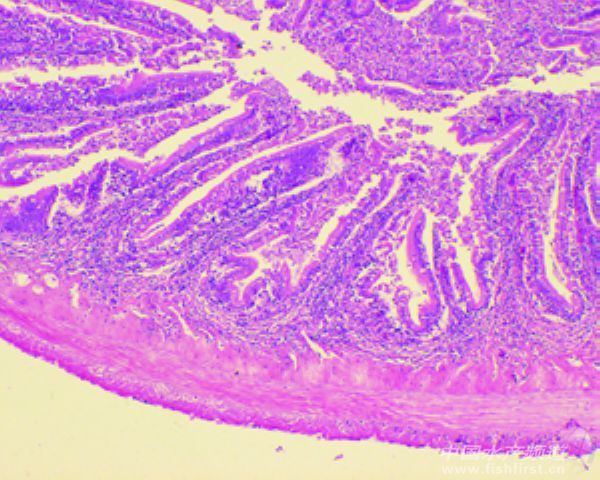

圖10 腸:上皮結構不清晰,淋巴細胞增生,輕微淤血;腸腔內有菌團